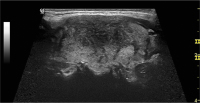

Abbildung 3: Detailaufnahme des linken Lappens zum Zeitpunkt der Erstvorstellung: im Längsschnitt das typische Muster einer subakuten Thyreoiditis de Quervain.